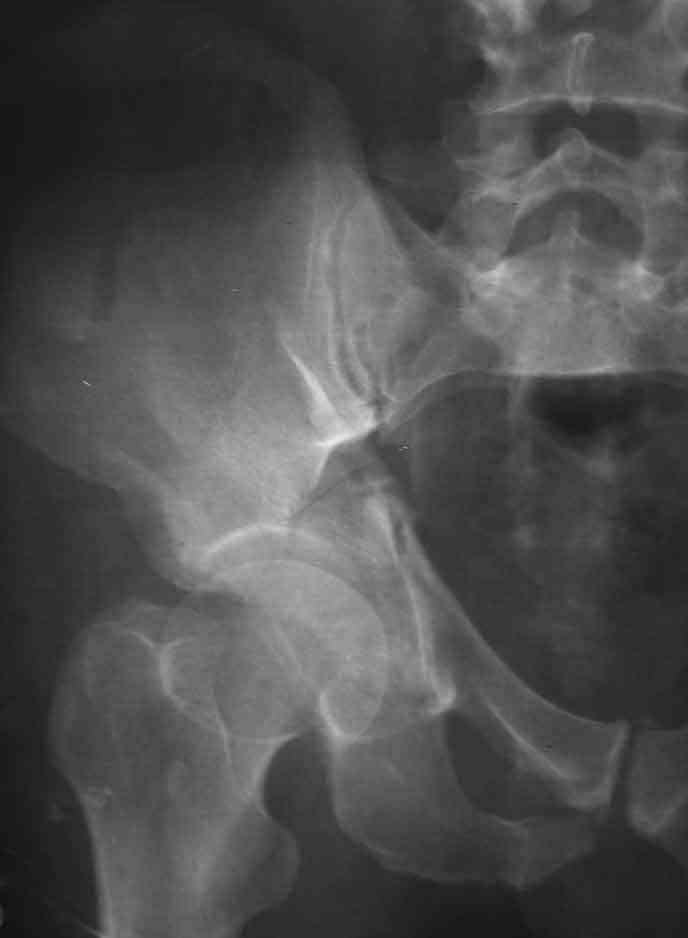

Dear Sir it looks quite difficult classify this fracture because the iliac view is not so clear.

In my opinion it is a column fracture because the obturator foramen is interrupted. There is a fracture of the posterior wall. If we assume the ap view as an iliac view it could be an anterior comun fracture plus posterior wall. It is difficult also to judge the head of the femur.

If you have not a CT scan I think that in order to have a good classification you should obtain a better view of the judet x rays.

From the x rays it appears like a bicolumnar fracture with iliac extension (AO C1).

I am sending another iliac view, and a marked version of the AP I already sent. In this AP, the

proximal part of the greater sciatic notch as well as the distal parts of the ilioischial and iliopubic lines are marked with a grey interrupted line. A white interrupted line marks what could be an exit through the obturator foramen, or so I assume.